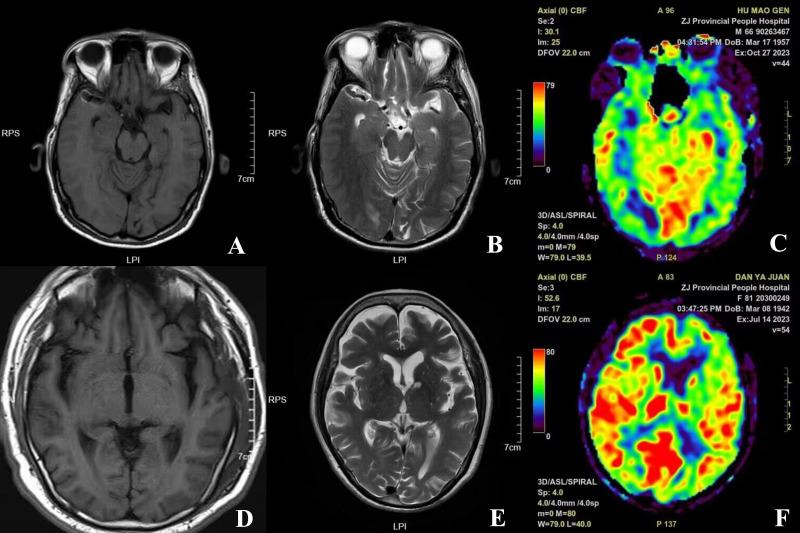

AD patients admitted to the 903 Hospital of the People's Liberation Army Joint Logistics Support Force from June 2020 to January 2023 were retrospectively selected as the study objects, and 65 healthy people who underwent physical examination during the same period were included in the control group. Subjects in both groups underwent 3.0 T magnetic resonance imaging (MRI) to observe their cerebral blood perfusion parameters. The level of cognitive function in both groups was assessed using the Montreal Cognitive Assessment (MoCA). Venous blood was collected from both groups, and the serum levels of brain-derived neuronal factor (BDNF) and glial cell-derived neurotrophic factor (GDNF) were measured by enzyme-linked immunosorbent assay (ELISA). The correlation of serum BDNF and GDNF levels with cerebral blood perfusion parameters and MoCA score in the AD group was analyzed using Spearman analysis.

The cerebral blood flow signal intensity of the left frontal lobe, right frontal lobe, left temporal lobe, right temporal lobe, left parietal lobe, right parietal lobe, left occipital lobe, and right occipital lobe of the observation group was significantly lower than that of the control group (p < 0.001). The visuospatial, executive functions, naming, attention, language function, abstract generalization ability, memory ability, orientation, and total MoCA scale scores were significantly lower than those of the control group (p < 0.001). The serum levels of BDNF and GDNF in the observation group were significantly lower than those in the control group (p < 0.001). The results of Spearman analysis showed that cerebral blood perfusion parameters of the left frontal lobe, right frontal lobe, left temporal lobe, right temporal lobe, left parietal lobe, right parietal lobe, left occipital lobe, and right occipital lobe were positively correlated with cognitive function scores in AD patients, serum BDNF and GDNF levels were positively correlated with cognitive function scores in AD patients, and the correlation was statistically significant (p < 0.05).

In AD patients, blood perfusion parameters and serum BDNF and GDNF levels were significantly lower than those of healthy people. Cerebral blood perfusion parameters of the left frontal lobe, right frontal lobe, left temporal lobe, right temporal lobe, left parietal lobe, right parietal lobe, left occipital lobe, and right occipital lobe, and BDNF and GDNF levels were positively correlated with cognitive function scores in AD patients.